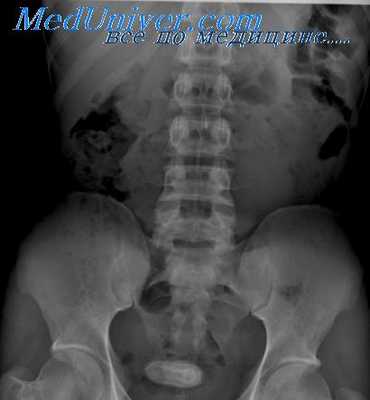

Язва двенадцатиперстной кишки сопровождается поздними (через 172—3 ч после еды), голодными, ночными острыми болями, обычно исчезающими после приема пищи и щелочей. Локализуются они преимущественно в луковице (95%), обычно в пределах 3 см от привратника, реже — в вертикальной части кишки и совсем редко — в ее нижнем горизонтальном отделе. Считается, что задняя стенка луковицы поражается примерно в 2 раза чаще, чем передняя, хотя имеются и другие данные: язвы на задней и передней стенках луковицы встречаются одинаково часто [Spjut, Navarrete, 1973].

Язвы задней стенки луковицы склонны к кровотечениям, а передней — к перфорациям. Мужчины болеют в 3 раза чаще женщин.

Чаще всего язвы располагаются по малой кривизне луковицы. При этом вид ниши определяется проекцией, в которой проводится рентгенологическое исследование: в первом косом положении (прямая проекция) ниша имеет вид контрастного пятна (депо бария), окруженного воспалительным валом слизистой оболочки (просветление),— фасная ниша, а во втором косом положении (боковая проекция) представляет собой конический выступ на контуре луковицы— профильная ниша. У детей и у полных пациентов желудок чаще расположен высоко и почти поперечно, поэтому получить снимки луковицы двенадцатиперстной кишки во второй косой проекции, а следовательно, распознать язву передней или задней стенки очень трудно.

Нередко с этим обстоятельством связано и расхождение результатов рентгенологического и эндоскопического исследований.

Язвенный процесс в луковице, как правило, сопровождается ее деформацией. Однако отсутствие деформации луковицы не исключает возможности длительного существования в ней язвенного процесса. В подобных случаях язвенный кратер остается в пределах слизистой оболочки, не проникая в мышечный слой луковицы.

Вид язвенной деформации луковицы во многом определяется наличием Рубцовых втяжений и выпячиваний ее стенки, сглаживания или укорочения большой или малой кривизны, удлинения или расширения ее заворотов. Однако локальный спазм, а также набухание слизистой оболочки в зоне расположения язвы существенно влияют на степень и характер деформации луковицы.